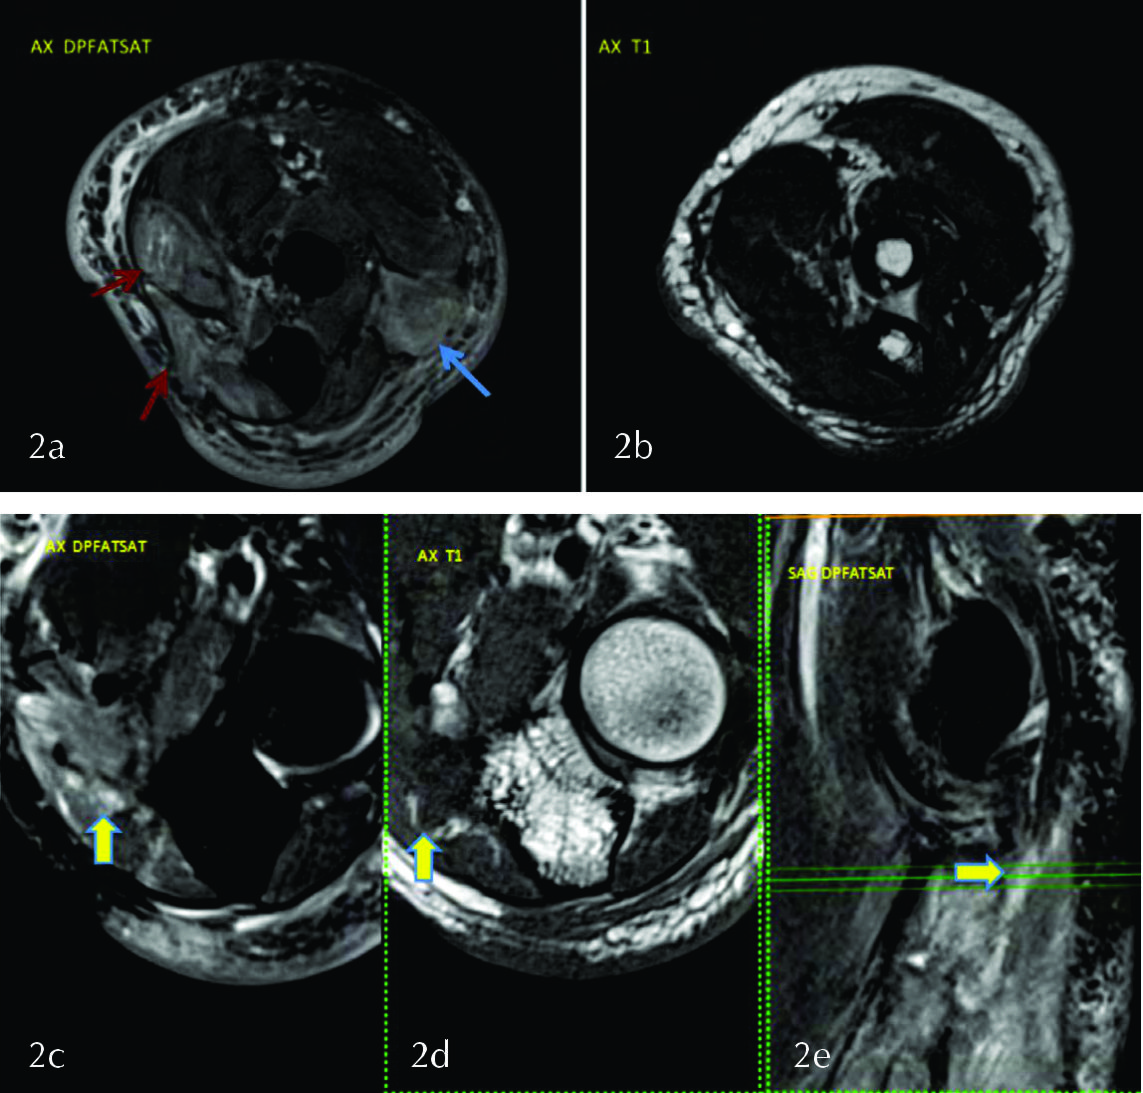

Paciente de 33 años de sexo masculino (SM), que consulta por omalgia derecha post esfuerzo. Se solicita una resonancia magnética (RM) de hombro derecho que muestra edema del musculo infraespinoso (fig. 1 a y b), sin edema en supra, subescapular ni redondo menor lo cual orienta a lesión del nervio supraescapular después de emitir la rama para el supraespinoso: topografía la lesión en la escotadura espino-glenoidea.

En la escotadura espinoglenoidea se identifica el nervio supraespinoso acompañado de la arteria supraespinosa (fig. 1 c,d,e).

Un corte mas abajo, axial y coronal posterior, se ve el nervio supraescapular y delante del mismo un quiste sinovial a nivel de la escotadura espino glenoidea que es la causa de la compresión del mismo (Fig. 1 f,g,h). El músculo infraespinoso presenta edema, sin atrofia en T1 compatible con denervación aguda o subaguda.

Cuando la denervación afecta solamente al infraespinoso se debe buscar la causa de compresión del nervio supraescapular a nivel de la escotadura espino glenoidea donde pueden observarse quistes (sinovial o para labral) que deben diferenciarse de várices u otras lesiones ocupantes de espacio (6).

Figura 1

Se observa leve hiperseñal del musculo infraespinoso (flechas en a y b). Se identifica el nervio supraescapular en la escotadura espino glenoidea (flechas) en los planos coronal (c) y axial (d y e), las líneas en c indican la altura del corte en d y e. Quiste sinovial ocupando la escotadura espino-glenoidea en los planos coronal (f) y axial (flechas en g y h).